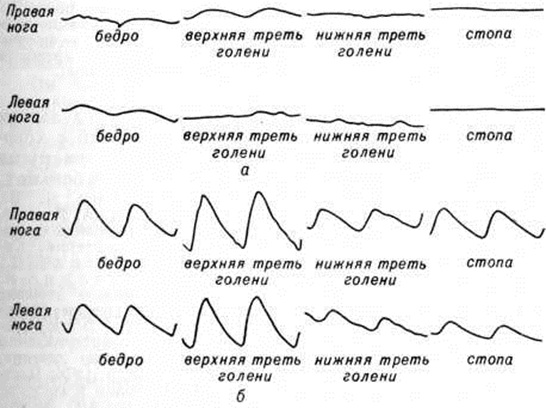

Инструментальные методы исследования — ультразвуковая флоуметрия, реовазо-, плетизмо-, осцилло-, сфигмография — выявляют снижение и запаздывание магистрального кровотока по артериям нижних конечностей (рисунок 3). Определение мышечного кровотока по клиренсу 133Xe выявляет его снижение, особенно резко при пробе с физических нагрузкой.